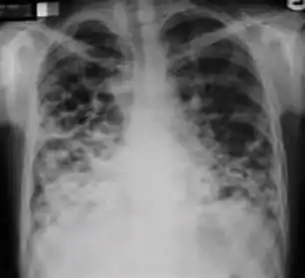

Dense homogenous opacity in right, middle and lower lobe of primary pulmonary TB.

Chest x-ray showing patchy opacification on the upper right and mid-zone lung with fibrotic shadows, as well as bilateral hilar lymphadenopathy.

Chest x-ray showing coarse reticulonodular densities on the lower right lung of post-primary pulmonary TB.

Chest x-ray of Ghon's complex of active tuberculosis